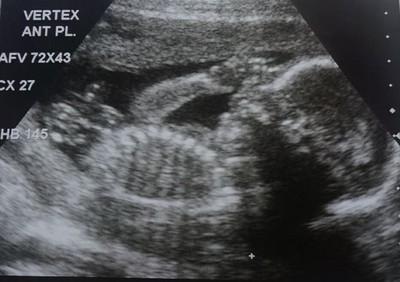

親愛的小袋鼠

20W3D 這是我的寶貝兒子---小袋鼠(像在摸鼻子,又像在吃雞腿)陽陽很喜歡小孩,所以在兩年前我們就取好男生小名要叫小袋鼠,女生叫小蜜桃,從12月初義大利蜜月旅行回來後就很積極做人,沒想到12月底就...